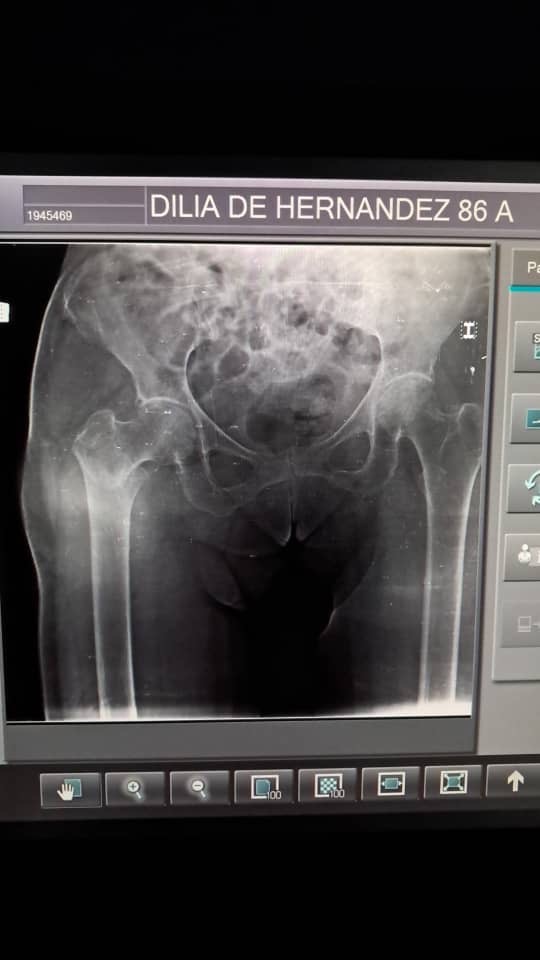

El pasado 4 de Julio, Dilia de 86 años —una madre, abuela y amiga querida por muchos— sufrió una caída en su hogar que le provocó una fractura de cadera derecha. Desde ese momento, su vida dio un giro inesperado. Ahora necesita ayuda para moverse, para dormir, incluso para las actividades más simples del día a día.

Los médicos han indicado que necesita una cirugía urgente, seguida de un proceso de rehabilitación intensiva para poder volver a caminar. Sin embargo, los costos del procedimiento, la terapia física y los implementos médicos necesarios son muy altos, y lamentablemente no están al alcance de su familia en este momento.